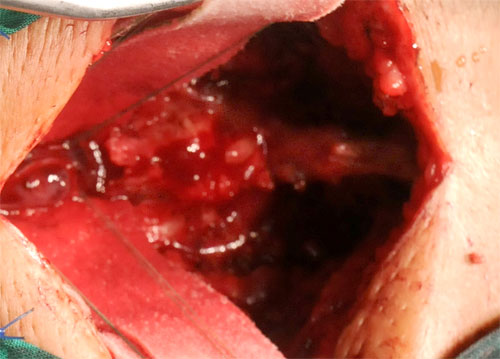

Karina Justiz Cabrera, había desarrollado durante el último trienio la estructura tumoral desde la décima vértebra toráxica (T-10) a la tercera lumbar (L-3), con localización entre la médula espinal y las estructuras que la cubren.

Los neurocirujanos citadinos abrieron el tiempo quirúrgico con el abordaje de la zona operatoria hasta la localización y extirpación del tumor, siempre acompañados por neurofisiólogos del hospital clínico quirúrgico de Santiago de Cuba, encargados de una de las dos avanzadas tecnologías empleadas: monitorización neurofisiológica pre, trans y postoperatoria, para prevenir en tiempo real cualquier posible daño a la médula o estructuras nerviosas.

La segunda fase empleó a neurocirujanos tuneros encargados de estabilizar la columna vertebral en la zona intervenida (también monitoreados por neurofisiologos), mediante fijación transpedicular, avanzada tecnología que emplea costosos materiales especiales (tornillos, láminas y varillas de titanio) con los cuales se mantienen las estructuras vertebrales en la correcta posición.